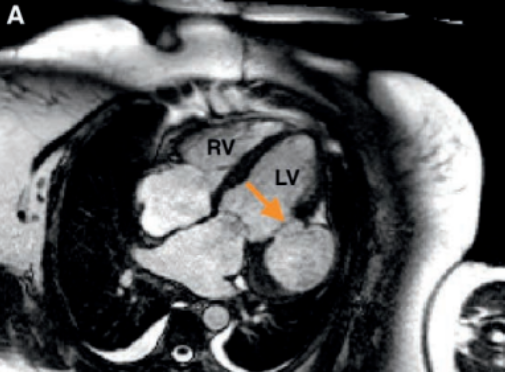

Ressonância magnética, evidenciando pseudoaneurisma (seta laranja)